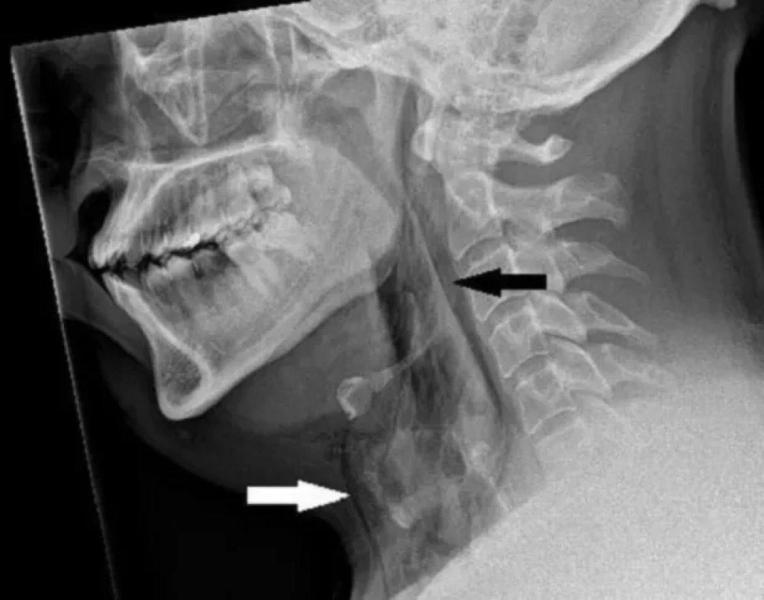

Пациент приехал в больницу, когда его шея распухла до таких размеров, что он уже практически не мог ей двигать. Врачи, осмотрев пострадавшего, отправили его на рентген. После изучения снимка выяснилось, что у шотландца произошел разрыв трахеи.

Медики объяснили, что если закрыть нос и рот во время чихания, то давление в верхних дыхательных путях может увеличиться до 20 раз. Это и произошло в ситуации с мужчиной, поэтому он получил такой тип травмы.